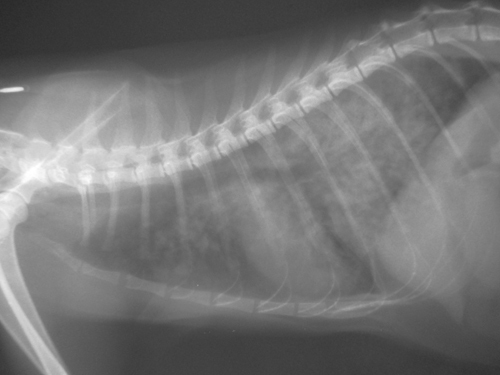

主題: 倒臥路邊的小黑桃 申請者姓名: 林玥蓉 花色: 申請日期: 2016-08-05 01:28:20 申請者部落格: 申請者臉書網址: 所在縣市/合作醫院: 高雄市/樂生動物醫院 治療費用: 18150元 需求人數: 20人 已結案 (2016-12-22 01:50:15) 報名人員: 咪太郎(已付款)、ERic YU(已付款)、Ping Hussard(已付款)、何春生 x3(已付款)、Lawrence x2(已付款)、Lawrence x2、lin789 x4(已付款)、Yi-Ling Yao(已付款)、Estee x2(已付款)、Estee x2、Estee、iamdavidga(已付款)、summer(已付款)、Jeffrey Chen(已付款)、可樂 x2(已付款)、 候補人員: 動物病情說明: 7/13那天因為一些因素前往前工作的地方發現有一隻貓倒在機車停車場垃圾場旁邊~一開始看到牠想說怎麼會這麼喘~是因為天氣熱嗎?靠近牠要看發現牠想逃走可是不太有力氣站起來~就知道牠狀況不好了(本人有養貓),裝箱時發現嘴角有紅紅的不知道是否是吐血...於是緊急送醫!黑桃到院時,呼吸急促,張嘴呼吸且幾乎無法站立,舌頭暗黑,呈現缺氧現象,初步照X光檢查,發現肺部有肺炎及肺水腫的跡象,驗血發現白血球過高有發炎現象...... 動物近況說明: 7/14探訪~依然喘息十分厲害~沒食慾!持續氧氣及營養點滴治療,若再沒食慾則須再安置食道胃管,以方便餵食並減少貓咪因強迫餵食而造成緊迫

7/30醫師講解新照的X光片與剛來時的做比較,相較之前器官較清晰可見,肺水腫消了不少~不見喘息食慾不錯但有拉肚子